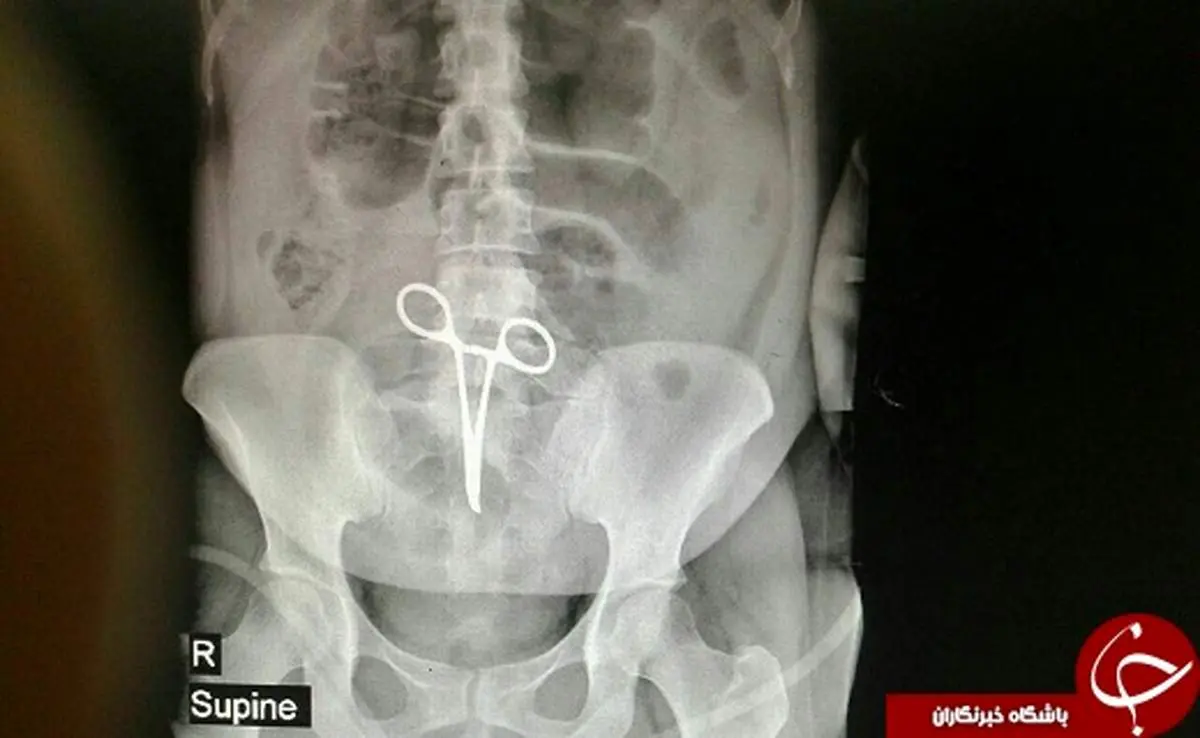

پارسینه: جاماندن ابراز جراحی ، زن ۳۵ ساله ای را برای بار دوم راهی اتاق عمل کرد .

قزوین - زن ۳۵ ساله به دلیل درد شکم به بیمارستان شهید رجایی قزوین مراجعه کرد و پس از معاینات پزشکی و تصویر برداری مشخص شد که در شکمش پنس جا مانده است .

زهرا فراهانی ، متخصص جراحی عمومی، در عمل جراحی ، سه ساعته ی دیگری پنس را خارج کرد .

به گفته مسوول اتاق عمل مرکز اموزشی - درمانی شهید رجایی قزوین ، این بیمار حدود دو ماه پیش در یکی از بیمارستان های شهریار تهران عمل جراحی کیست تخمدان انجام داده بود که پنس در شکمش جا ماند .

ریحانه چگینی اضافه کرد : در حال حاضر ، حال عمومی بیمار خوب است و تحت مراقبتهای ویژه بعد از عمل در بخش جراحی زنان بستری است .